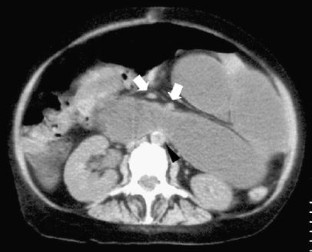

Crohn disease obstruction of the biliopancreatic limb in a patient operated for biliopancreatic diversion for morbid obesity

Although rare, patients with biliopancreatic diversion for morbid obesity will be subject to obstruction of the biliopancreatic limb. This condition is commonly due to postoperative adhesions and intussusception and usually presents with misleading clinical and radiographic features that can delay the diagnosis and the treatment. We recently encountered a patient with obstruction of the biliopancreatic limb due to involvement from Crohn disease. We report this case to highlight the clinical and imaging findings of this rare condition.

Fig. 2